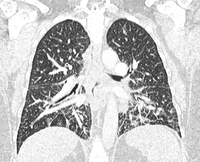

Ct scan of the lung